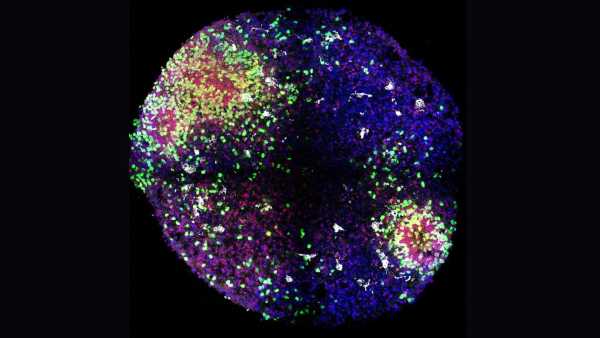

«Мінімозки» розкривають секрети формування ключових клітин мозку в утробі матері

«Мінімозки» розкривають секрети формування ключових клітин мозку в утробі матері

«Мінімозки» розкривають секрети формування ключових клітин мозку в утробі матері